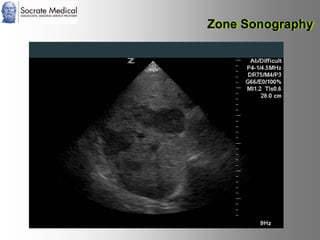

Il documento presenta la tecnologia della zone sonography, che promette una rivoluzione nel campo degli ultrasuoni, superando i limiti dei sistemi tradizionali grazie a metodi di acquisizione dati più veloci e una gestione delle informazioni migliorata. Questa tecnologia consente una maggiore definizione dell'immagine, una riduzione degli artefatti e un'ottimizzazione del processo diagnostico, con vantaggi in termini di tempo e costi. Inoltre, il channel domain processing e la zone speed technology offrono applicazioni avanzate e miglioramenti nella sicurezza diagnostica.